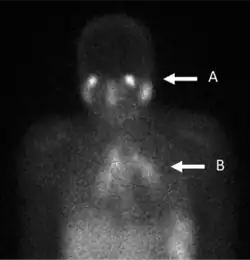

Scintigraphie au gallium

La scintigraphie au gallium est un type de test de médecine nucléaire utilisant un gallium-67 (67Ga) ou gallium-68 (68Ga) radio-pharmaceutique pour obtenir des images d'un type spécifique de tissu, ou l'état de maladie tissulaire. Les sels de gallium peuvent être utilisés comme citrate de gallium et nitrate de gallium. La forme de sel n'est pas importante, car c'est l'ion de gallium libre dissous Ga3+ qui est actif[1]. Les sels 67Ga et 68Ga ont des mécanismes de captage similaires[2]. Le gallium peut également être utilisé sous d'autres formes, par exemple 68Ga-PSMA est utilisé pour l'imagerie du cancer de prostate. L'émission gamma de gallium-67 est détectée par une caméra gamma, tandis que l'émission de positons de gallium-68 est détectée par tomographie par émission de positons (PET).

Les sels de gallium sont absorbés par les tumeurs, l'inflammation et les infections aiguës et chroniques[3],[4] permettant l'imagerie de ces processus pathologiques. Le gallium est extrêmement utile pour l'imagerie de l'ostéomyélite impliquant la colonne vertébrale et pour l'imagerie d'infections plus anciennes et chroniques pouvant être à l'origine d'une fièvre d'origine inconnue[5],[6].